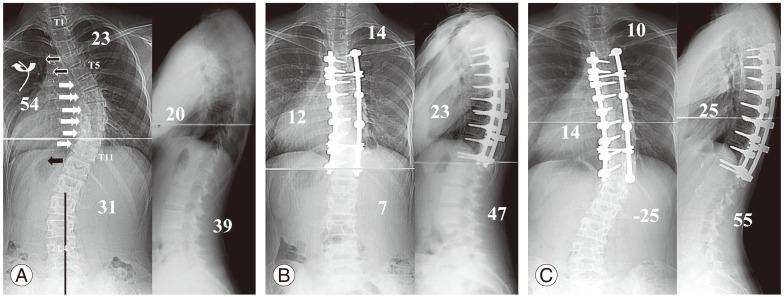

We retrospectively analyzed 160 patients with thoracic adolescent idiopathic scoliosis treated by pedicle screw instrumentation and rod derotation. Patients who had a distal fusion level between T11 and L1 were divided into two groups: the DVR group versus the No-DVR group. Each group was divided into subgroups depending on the lumbar modifier used: the DVR-A, B, and C groups versus the No-DVR-A, B, and C groups. The DVR-A group was subdivided into two subgroups depending on the direction of screw rotation in the LIV: the DVR-A-O group (opposite direction) and the DVR-A-S group (same direction).

There were no significant differences in the preoperative curve characteristics between the two groups. The preoperative lumbar curve was corrected in 70% of the patients in the DVR group and in 56% in the No-DVR group. Spontaneous coronal correction of the lumbar curve was better in the DVR-A-S group than that in the No-DVR-A group. However, the DVR-A-O group had the higher incidence of adding-on deformity. The DVR-B and C groups showed better spontaneous correction of lumbar coronal magnitude, apical vertebral translation, and rotation and the LIV tilting.

In lumbar modifiers B and C, screws in the LIV have to be rotated opposite to the direction of the screw rotation of the main thoracic curve; however, in modifier A, the screws have to be rotated in the same direction.

我们回顾性分析了160例接受椎弓根螺钉内固定和棒旋转术治疗的青少年特发性脊柱侧凸患者。远端融合水平在T11和L1之间的患者分为两组:DVR组和非DVR组。每组根据使用的腰椎修正器分为亚组:DVR - A、B和C组与非DVR - A、B和C组。DVR - A组根据LIV中螺钉旋转方向再分为两个亚组:DVR - A - O组(相反方向)和DVR - A - S组(相同方向)。

两组术前曲线特征无显著差异。DVR组70%的患者术前腰椎曲线得到矫正,非DVR组为56%。DVR - A - S组腰椎曲线的自发冠状面矫正优于非DVR - A组。然而,DVR - A - O组附加畸形的发生率更高。DVR - B组和C组在腰椎冠状面大小、顶椎平移、旋转和LIV倾斜方面显示出更好的自发矫正效果。

在腰椎修正器B和C中,LIV中的螺钉必须与主胸弯螺钉旋转方向相反;然而,在修正器A中,螺钉必须朝相同方向旋转。